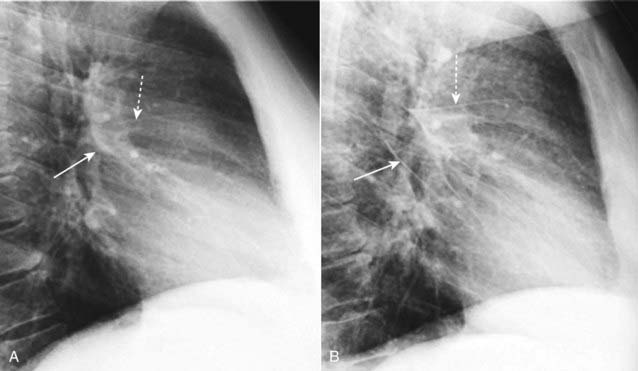

image

Figure 9-2 Pericardial effusions, small and large.

A, Fluid first begins to accumulate in the dependent portions of the pericardial space which is posterior to the left ventricle in the supine position (solid white arrow). B, As the effusion increases in size, it fills the pericardial space and encircles the heart (dotted white arrows). Conventional chest radiographs may show an enlarged cardiac silhouette but cannot differentiate the density of the heart from the effusion.